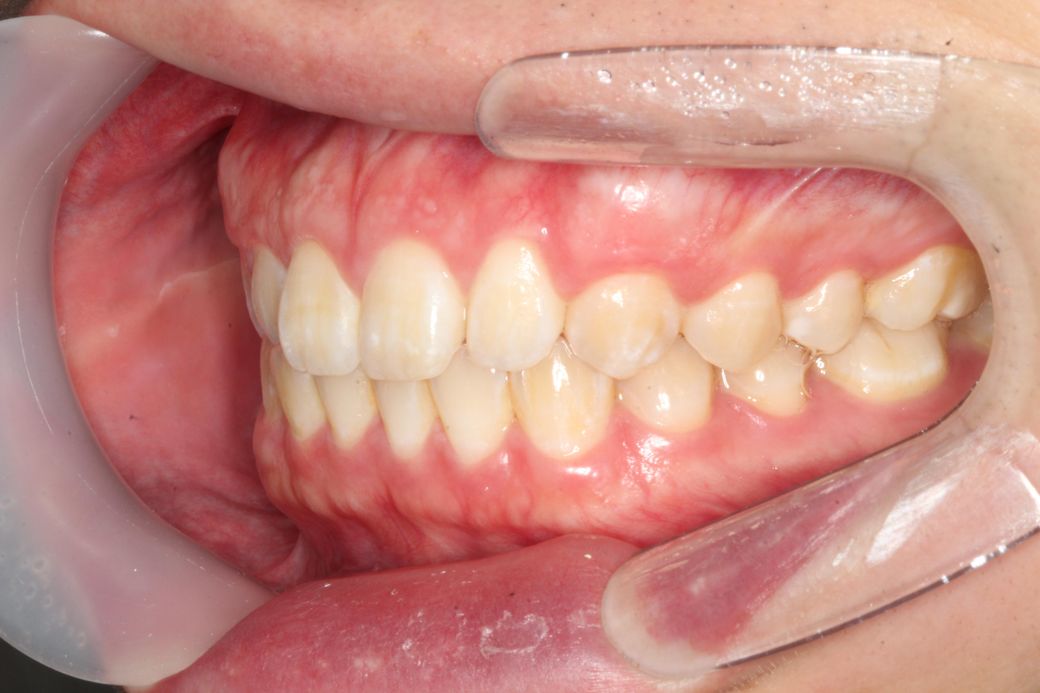

턱이 왼쪽으로 canting 되어있어도 어금니 교합이 맞을수 있나요?

턱이 왼쪽으로 비대칭이 약간 있는데 그래도 어금니 교합이 맞을수있나요?

주관적인 생각으로 약간 아랫뼈? 치아?들이 전체적으로 왼쪽으로 이동한 느낌인데 이러면 어금니 교합도 틀어지지않나요?

사진상 왼쪽어금니들은 윗아래 옆면 딱붙는 느낌이면

오른쪽은 옆면이 공간이 남는 느낌? 입니다

-현재 제 교합이 정상적인건지 궁금합니다

• 2번 째 사진

일전에도 문의주신 것으로 기억합니다. 현재 좌측으로 canting 되어 있으나 이는 사람에 따라서는 치료의 대상이 아닐 수도 있습니다. 모든 사람은 양쪽으로 모두 대칭인 수평인 경우는 거의 없으며 한쪽으로 canting되어 있는 경우가 많습니다. 이때 canting 범위에 따라 정상일 수도 있고 정상이 아닐 수도 있으나 이는 본인이 심미적으로 전혀 문제가 되지 않는다고 본다면 치료를 하지 않아도 됩니다.

현재 교합이 완전하다고 할 수는 없습니다. 따라서 교정적인 힘으로 치열을 바꿀 수는 있어 보여도 상당히 어려운 과정을 거쳐야할 것으로 보이며 교정 전 후가 크게 달라지지 않을 수 있어 보입니다. 발치 교정도 현재로서는 애매하고 비발치 교정에도 한계가 있어 보입니다. 즉 정상범주에서 특별히 많이 벗어나는 것이 아니라는 것입니다.

이상적인 교합이면 가장좋겠지만, 작성자님의 상태의 교합이 크게 문제가 되어 보이진 않습니다. 다만, 기능적으로 문제가 있다면 교정을 고려해보셔도 되지만, 기능상으로 크게 문제가 없다면 그냥 지내셔도 상관없을것같습니다.